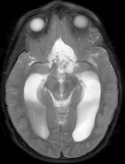

Note that term 2 is sparse if there are no major changes between and , both images have similar grey-level intensities and they are spatially matched. While these conditions meet in many application of dynamic imaging, such as prior image constrained compressed sensing (PICCS) in CT (Chen et al., 2008; Lauzier et al., 2012) and dynamic MRI (Jung et al., 2009; Lustig et al., 2006; Gamper et al., 2008; Yip et al., 2014), in longitudinal MRI none of these requirements are guaranteed. While there are solutions for miss-registration and variable grey level intensities (see Section 4), the temporal similarity in longitudinal MRI is a-priori unknown. Although longitudinal MRI may exhibit temporal similarity (Samsonov et al., 2010), we have to take into account that in many cases the follow-up scan may exhibit substantial changes with respect to the baseline scan. Such cases may occur, for example, if a surgical intervention was applied between the time points or if there is a major progressive or therapy response. Figure 2 shows two representative examples.

Baseline 4 months Baseline 3 months

Hydrocephalus GBM